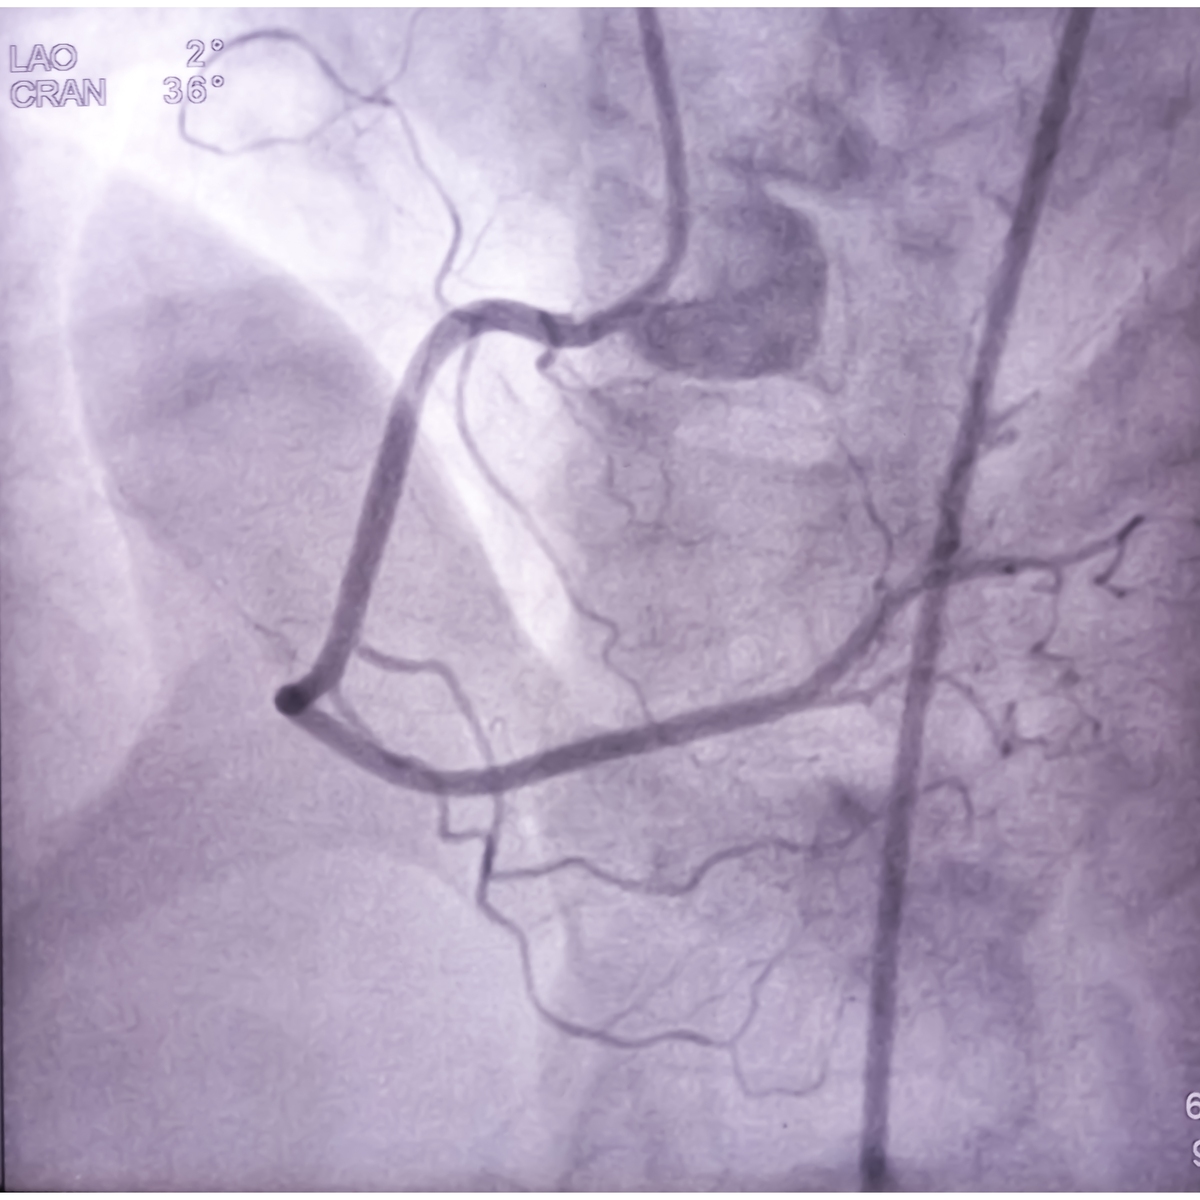

首先,冠状动脉造影是目前最常用的冠状动脉成像技术。通过在患者体内注入造影剂,可以清晰地显示冠状动脉的血流情况,包括狭窄、堵塞等病变。这种技术具有高分辨率、高灵敏度和高特异性的优点,可以帮助医生准确诊断冠心病等心血管疾病。